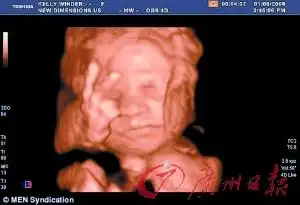

英一女子怀孕27周 胎儿摆出不雅手势(图)